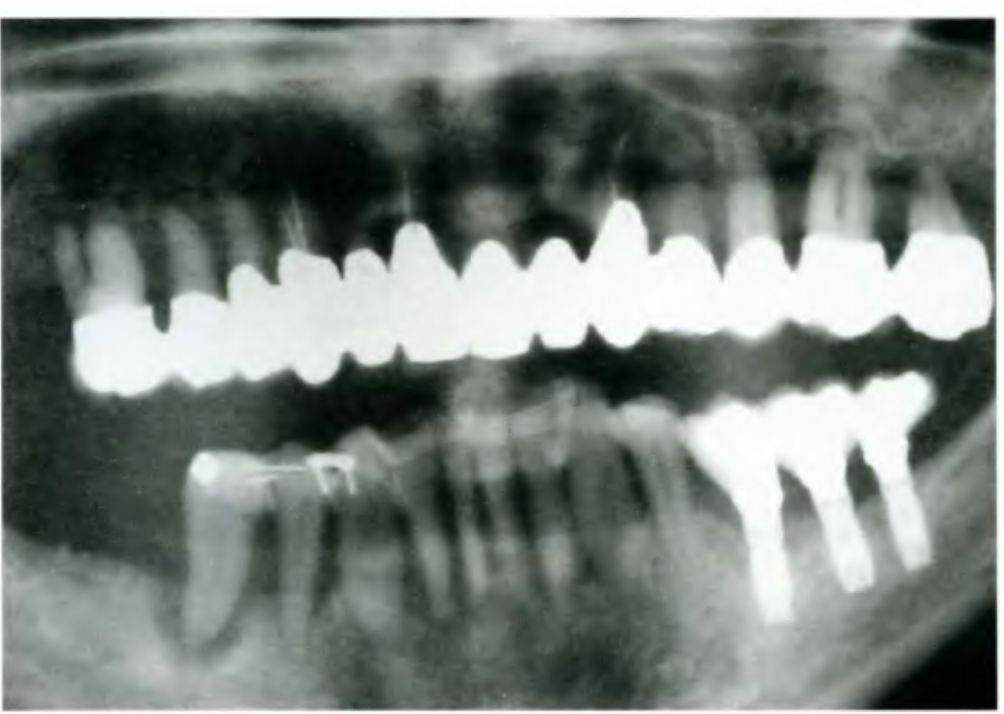

Полная диагностика, включая клиническое обследование, определение параметров пародонта, расчет пародонтологических индексов и полную серию прицельных снимков.